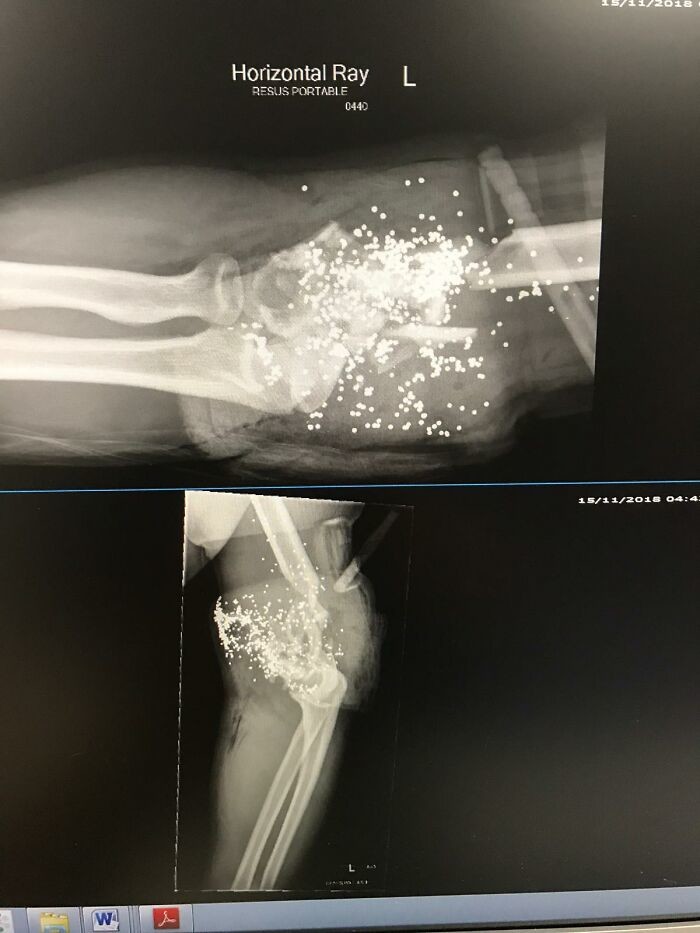

10. Последствия выстрела в локоть из дробовика 12-го калибра на рентгеновском снимке